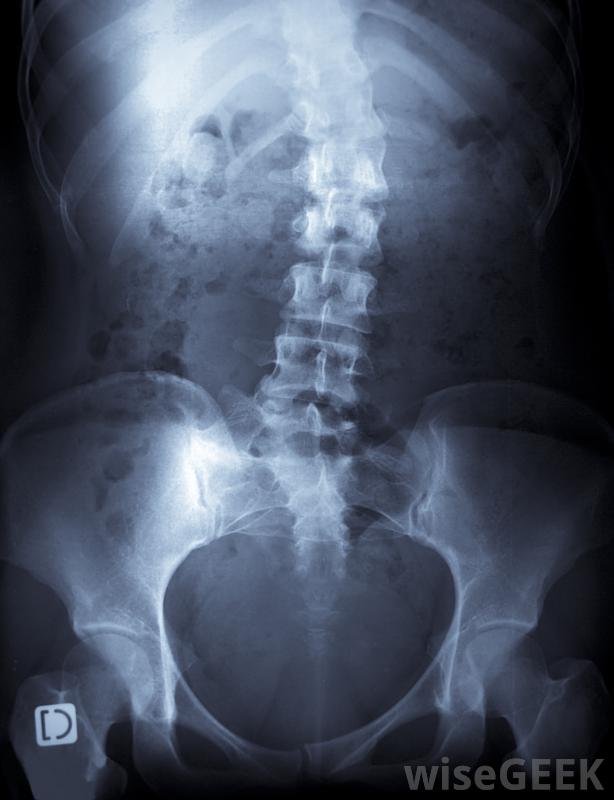

脊柱侧凸可以戴上背带医生可以检查病人的身体症状,摸摸脊柱和周围组织,并给背部拍x光片。为了做出正确的诊断,医生可能会进行额外的检查,以检查潜在的病因。有些脊柱侧凸是先天性缺陷、神经肌肉疾病和关节炎造成的不过,这种情况通常是特发性的,一些婴儿先天性和特发性脊柱侧凸的病例在出生后的几年内就自行纠正了。6岁以下的儿童通常不接受脊柱侧凸的治疗,除非他们的曲线非常严重。对于年龄较大的儿童和青少年来说,每天戴几小时特制的背带被认为是最好的治疗方法。就像牙齿上戴的牙套一样,背托施加的压力很小,可以逐渐拉直脊柱。在骨骼静止的时候戴上支架在发育过程中,椎骨更容易长成一条直线。对于成人、有严重曲线的儿童,手术通常被认为是脊柱侧凸的最佳治疗方法,以及患有神经肌肉疾病的所有年龄段的人。一组熟练的外科医生可以进行一项非常精细的手术,将椎骨融合在一起,从而防止脊柱弯曲恶化。手术通常对缓解疼痛和其他症状非常有效,虽然完全纠正这种情况的手术很少见,但人们一生中仍可能会经历背痛通过加强锻炼和定期与医生会面,患者通常可以学会应对自己的状况并享受定期活动。